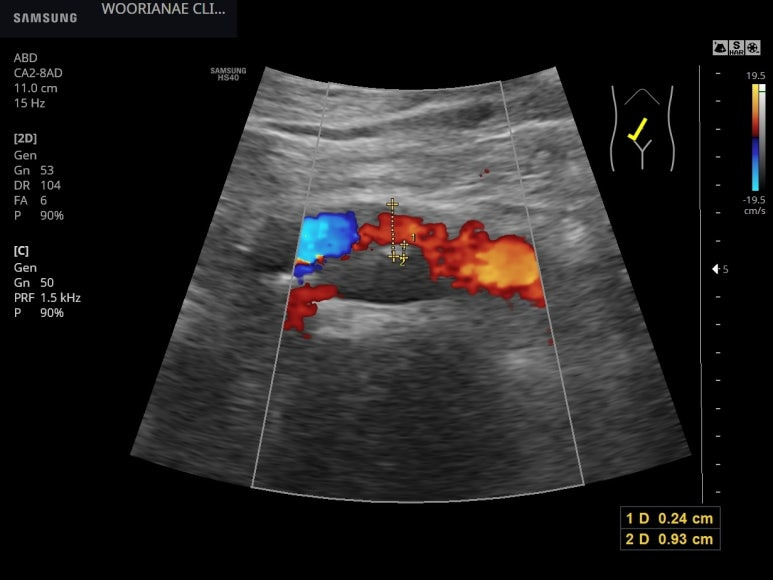

흡연하는 분으로 좌측 경동맥 아래쪽은 내막이 균일하게 두껍고...

같은 맥락에서 복부 초음파시 우측 장골동맥에 경화반이 관찰되었다.